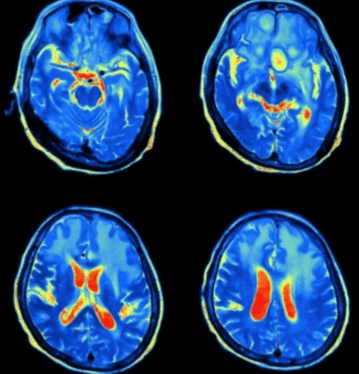

Νεγλαιρίαση: Το υπουργείο Υγείας του Ισραήλ ανακοίνωσε την Παρασκευή πως ένας 36χρονος πέθανε εξαιτίας επιπλοκών μηνιγγοεγκεφαλίτιδας αφότου προσβλήθηκε από μια σπάνια αμοιβάδα η οποία «τρώει» τον εγκέφαλο.

Σύμφωνα με πληροφορίες, το θύμα από το βόρειο Ισραήλ, που δεν είχε υποκείμενα νοσήματα, πέθανε από νεγλαιρίαση – γνωστή επίσης ως πρωτογενής αμοιβαδική μηνιγγοεγκεφαλίτιδα (primary amoebic meningoencephalitis ή PAM) – μια σπάνια λοίμωξη του εγκεφάλου, η οποία προκαλείται από την αμοιβάδα Naegleria fowleri.

Στα πρώτα στάδια της λοίμωξης PAM μέσω της ρινικής κοιλότητας, τα συμπτώματα μπορεί να περιλαμβάνουν έντονο πονοκέφαλο, πυρετό, ναυτία και έμετο.

Καθώς η λοίμωξη επιδεινώνεται, τα συμπτώματα – που εμφανίζονται 1-9 ημέρες μετά την έκθεση – μπορεί να εξελιχθούν σε επιληπτικές κρίσεις ή παραισθήσεις.